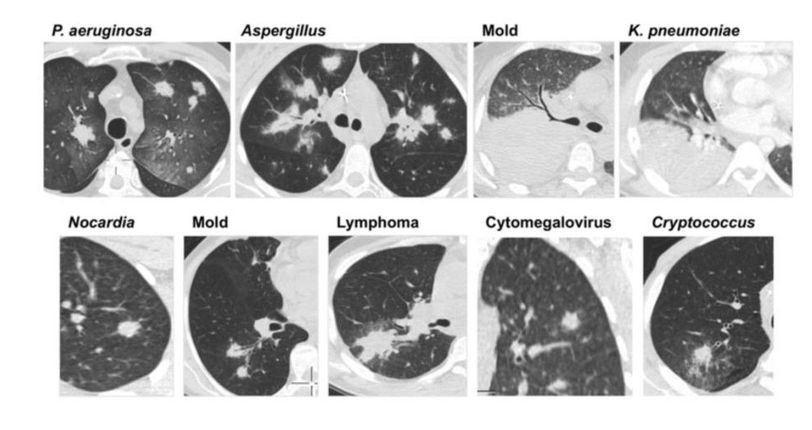

Pneumonia

Viral

Lymphoma

Infectiousdisease

Bacterial infections. Bacteria are single-celled organisms with their instructions written on a small piece of DNA. Bacteria are all around us, including inside of our body and on our skin. Many bacteria are harmless or even helpful, but certain bacteria release toxins that can make you sick.

Fungal infections. Like bacteria, there are many different fungi. They live on and in your body. When your fungi get overgrown or when harmful fungi get into your body through your mouth, your nose or a cut in your skin, you can get sick.